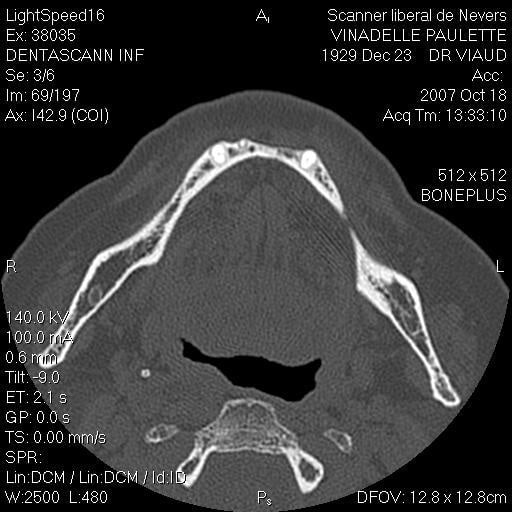

Je suis désolé mais le seul problème que j’ai eu sur un maxillaire inférieure (celui que j’ai mis en photo d’ailleurs) c’est une rupture de la table interne en 33 34 (suite à un mouvement inopportun de la patiente, ce que j’aurais du prévoir) j’ai repris le cas 3 mois plus tard et no problème.

scan te montrant la façon dont je contourne les obstacles